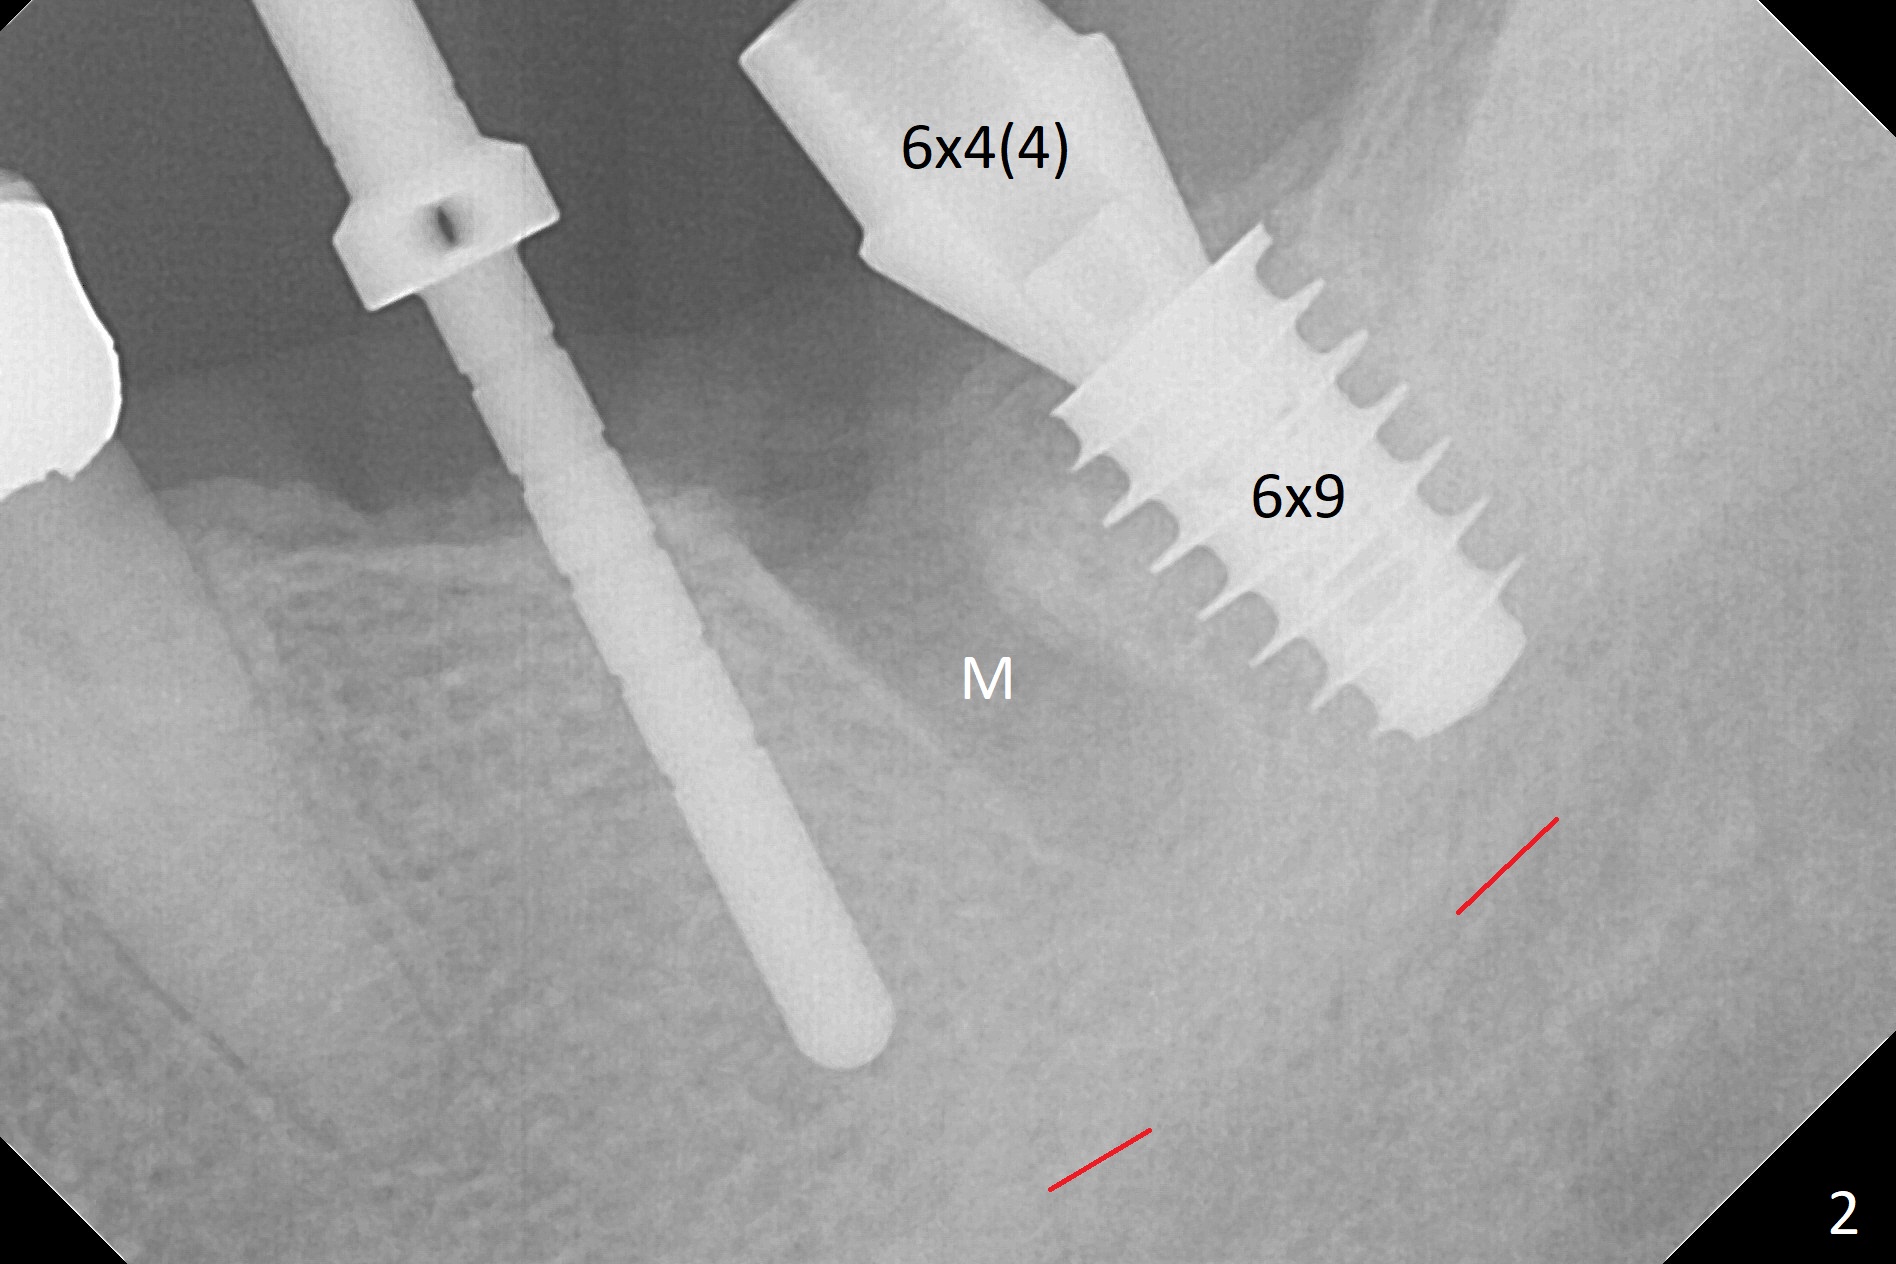

After extraction of the residual root at #18 (Fig.1), the septum is narrow, while the distal socket seems to be the most appropriate site for implant placement (Fig.2 (M: mesial)).  In fact the implant needs to tilt slightly distally (relative to the original trajectory of the distal socket, Fig.3 green) to occlude with the opposing tooth.  The implant at #19 could be placed more mesially (Fig.4 (*: Vera Graft)).